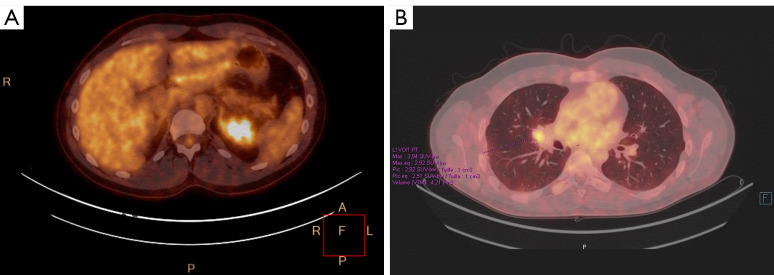

背景:IV期非小细胞肺癌不是一个可治愈的阶段。然而,一种局部治疗原发肿瘤的新方法可能会提高无进展生存期。放疗或手术的选择,以及这些治疗的最佳时机仍有待确定。我们在这里报告第一例,据我们所知,一个多转移患者在新辅助阿勒替尼治疗后接受巩固手术,导致完全的病理反应。病例描述:该患者是典型的致癌改变人群,如间变性淋巴瘤激酶(ALK)重排,年轻,不吸烟;然而,他是男性。支气管内窥镜检查证实支气管肺腺癌,免疫组化显示ALK强表达。我们启动了alectinib作为转移性疾病的一线治疗;然而,由于诱导的低转移性疾病,在多学科委员会上讨论了原发肿瘤的局部治疗。行肺叶切除术,组织学检查证实完全病理反应。由于缺乏可用数据,佐剂alectinib持续时间未确定。结论:该病例提示,局部治疗,即使是IV期患者,在对全身治疗有最佳反应的时候进行,可能会改善无进展生存期,甚至可能是治愈的一瞥。

Case description: The patient was, as is typically observed in populations with oncogenic alterations such as anaplastic lymphoma kinase (ALK) rearrangements, a young and non-smoker; however, he was male. Bronchial endoscopy confirmed the diagnosis of bronchopulmonary adenocarcinoma with strong ALK expression demonstrated by immunohistochemistry. We initiated alectinib as first-line treatment for metastatic disease; however, due to the induced oligo-metastatic disease, a local treatment of the primary tumor was discussed during multidisciplinary board. Lobectomy was performed and histological examination confirmed the complete pathological response. Adjuvant alectinib was continued for unspecified duration due to the lack of available data.